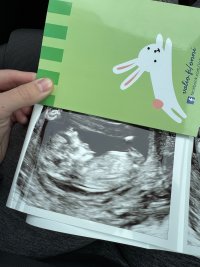

Kyllä tää kovasti tytöltä näyttää…Olisi myös tämä kuva

Tässä ei näy nubia.

Ei näy mun silmään.

Näkyisköhän tässä?Ei näy mun silmään.![]()